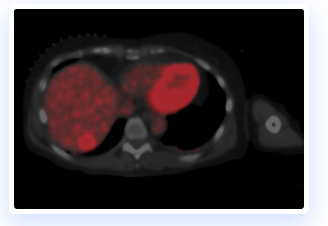

The IGTFusion System utilizes patented software algorithms to automatically align images from single and multiple image sources.

IGTFusion can visualize and register 3D image data from multiple modalities, including CT, PET, and MR images automatically.